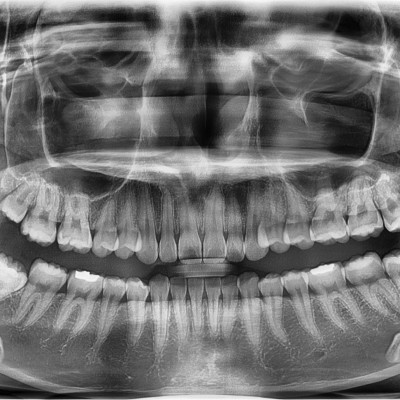

#38,48 (#37,47 포함) 사랑니 발치 #38,48 (#37,47 포함) 사랑니 발치 구강 외과 전문의가 당일 발치했습니다. -------------..

작성자 이턱이 작성일 03-12 조회 24